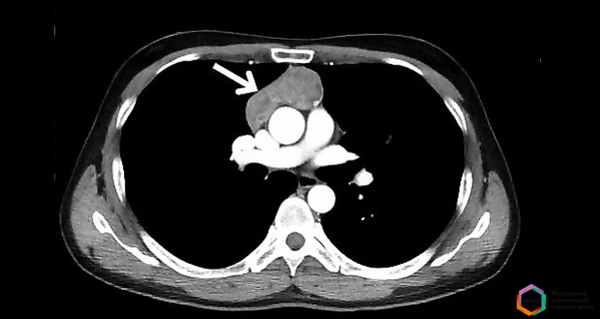

Большинство тимом можно обнаружить с помощью обычной рентгенографии. Опухоль выглядит как тень с ровными краями в верхней половине грудной клетки. Она частично перекрывает тень от сердца, находится преимущественно справа или слева.

Компьютерная томография помогает уточнить размеры и локализацию тимомы, выявить небольшую опухоль, которая не обнаруживается во время рентгенографии. Увеличение тимуса на снимках, полученных с помощью КТ, также чаще всего свидетельствует о том, что в вилочковой железе присутствует тимома.

Компьютерная томография предпочтительна у пациентов с миастенией. Наиболее информативны снимки, выполненные с внутривенным контрастированием. Они помогают оценить расположение тимомы по отношению к крупным кровеносным сосудам, ее кровоснабжение, правильно спланировать операцию.